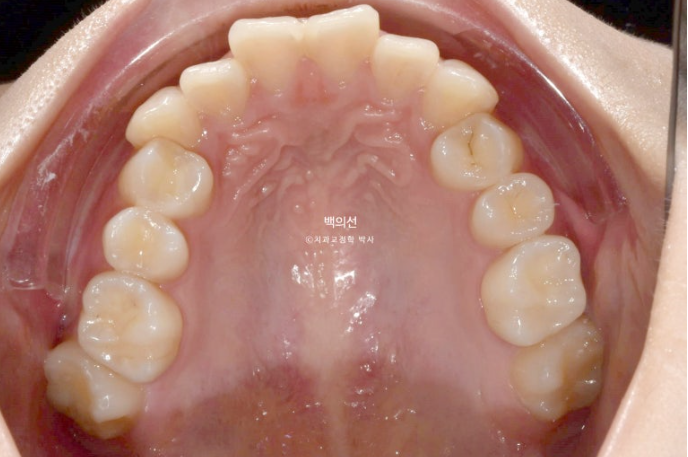

23.05

맨 뒤 큰어금니는 뒤로 나있습니다.